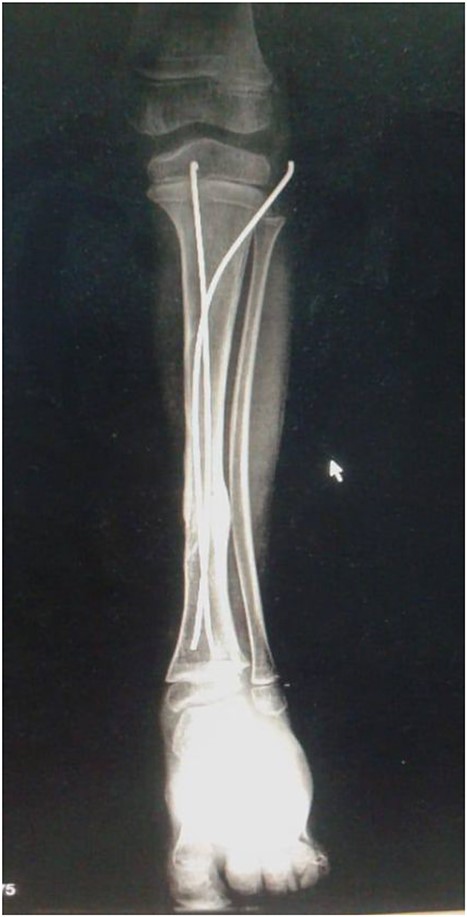

The decision to perform limb salvage surgery was made despite parental refusal and the consideration of the patient’s age. Initial debridement was performed in the supine position, with dislocations and fractures reduced and fixed using K-wires (Fig. 2). A temporary skewer was placed between the foot and the leg components to ensure stability. The patellar tendon, posterior muscles, and skin flap were meticulously sutured (Fig. 3). Postoperative follow-up showed satisfactory capillary refill, moderate sensation, and return of the anterior tibial artery pulse within three days. Progressive wound healing was observed over a month, allowing partial weight-bearing ambulation at 2 months (Fig. 4). Complete leg bone healing was achieved at 6 months, with removal of the flexible nail and restoration of the full range of motion and sensation (Fig. 5).

Displays the leg after suturing the skin flap, along with the X-ray image following the installation of the K-wires.